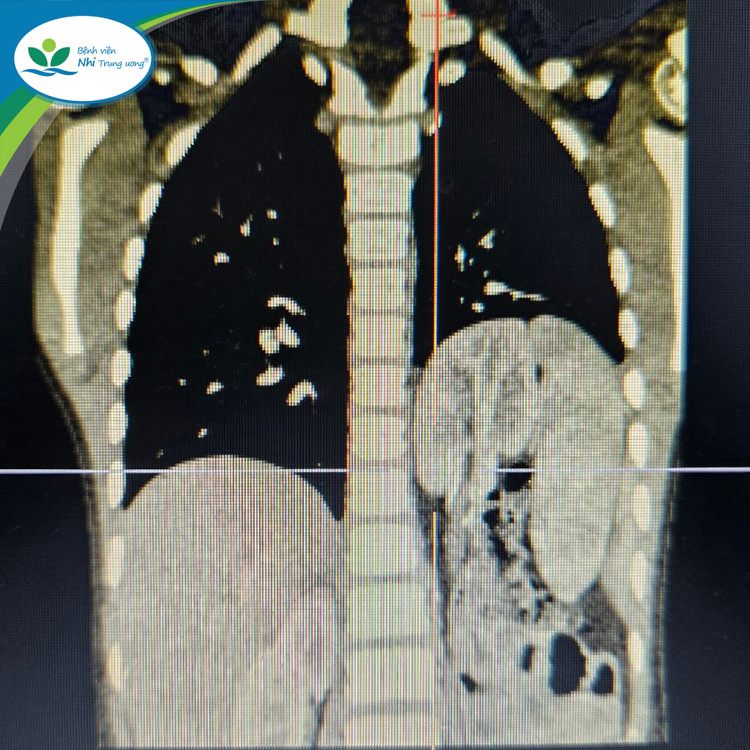

| Hình ảnh chụp thoát vị hoành trái bẩm sinh với tạng thoát vị là lách, ruột non, đại tràng và kèm theo thận lạc chỗ trên lồng ngực của trẻ |

Trước đó, trẻ vào viện vì đau tức ngực và nhiễm khuẩn hô hấp tái diễn nhiều lần. Trẻ được các bác sĩ thăm khám lâm sàng, chụp X-quang và chụp cắt lớp vi tính lồng ngực, hình ảnh quan sát thấy là thoát vị cơ hoành bên trái với tạng thoát vị là lách, đại tràng, ruột non, kèm theo thận trái lạc chỗ trên lồng ngực.